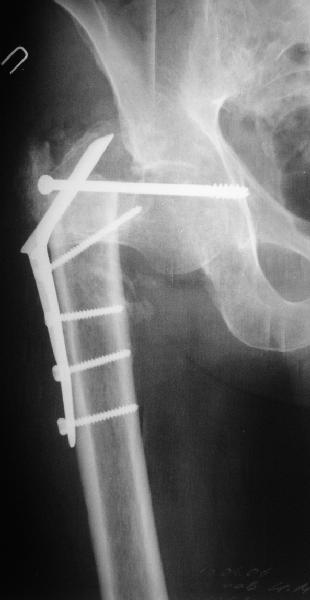

В этом случае, по-моему, аппаратный этап не был уж настолько важен. При использовании DHS или клинковой пластины при таком исходном положении отломков можно было делать и одномоментную коррекцию.

Срубить латеральную стенку периферического отломка для облегчения вальгизации.

В приложении пример пациента, близкого по картине к тому, что представил Виктор (варус и смещение периферического отломка на поперечник кзади). Сделали как раз то, что Виктор исходно намеревался - аппаратная коррекция и затем гамма.